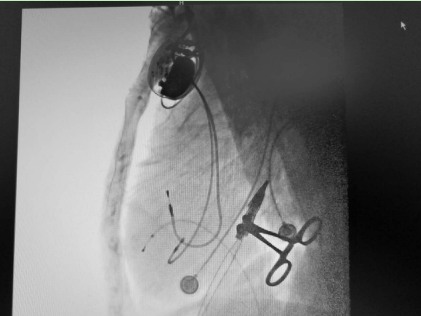

3天后成功植入心脏永久起搏器——熬过了前面的生死难关,3天后,朱彬为老人实施了双腔心脏永久起搏器植入术,并程控相关参数以满足患者个体状态所需,手术过程顺利,疾病得到根治。7天后,老人康复出院,出院后长期门诊随访未再出现晕厥,生活能够自理。

起搏器成功植入